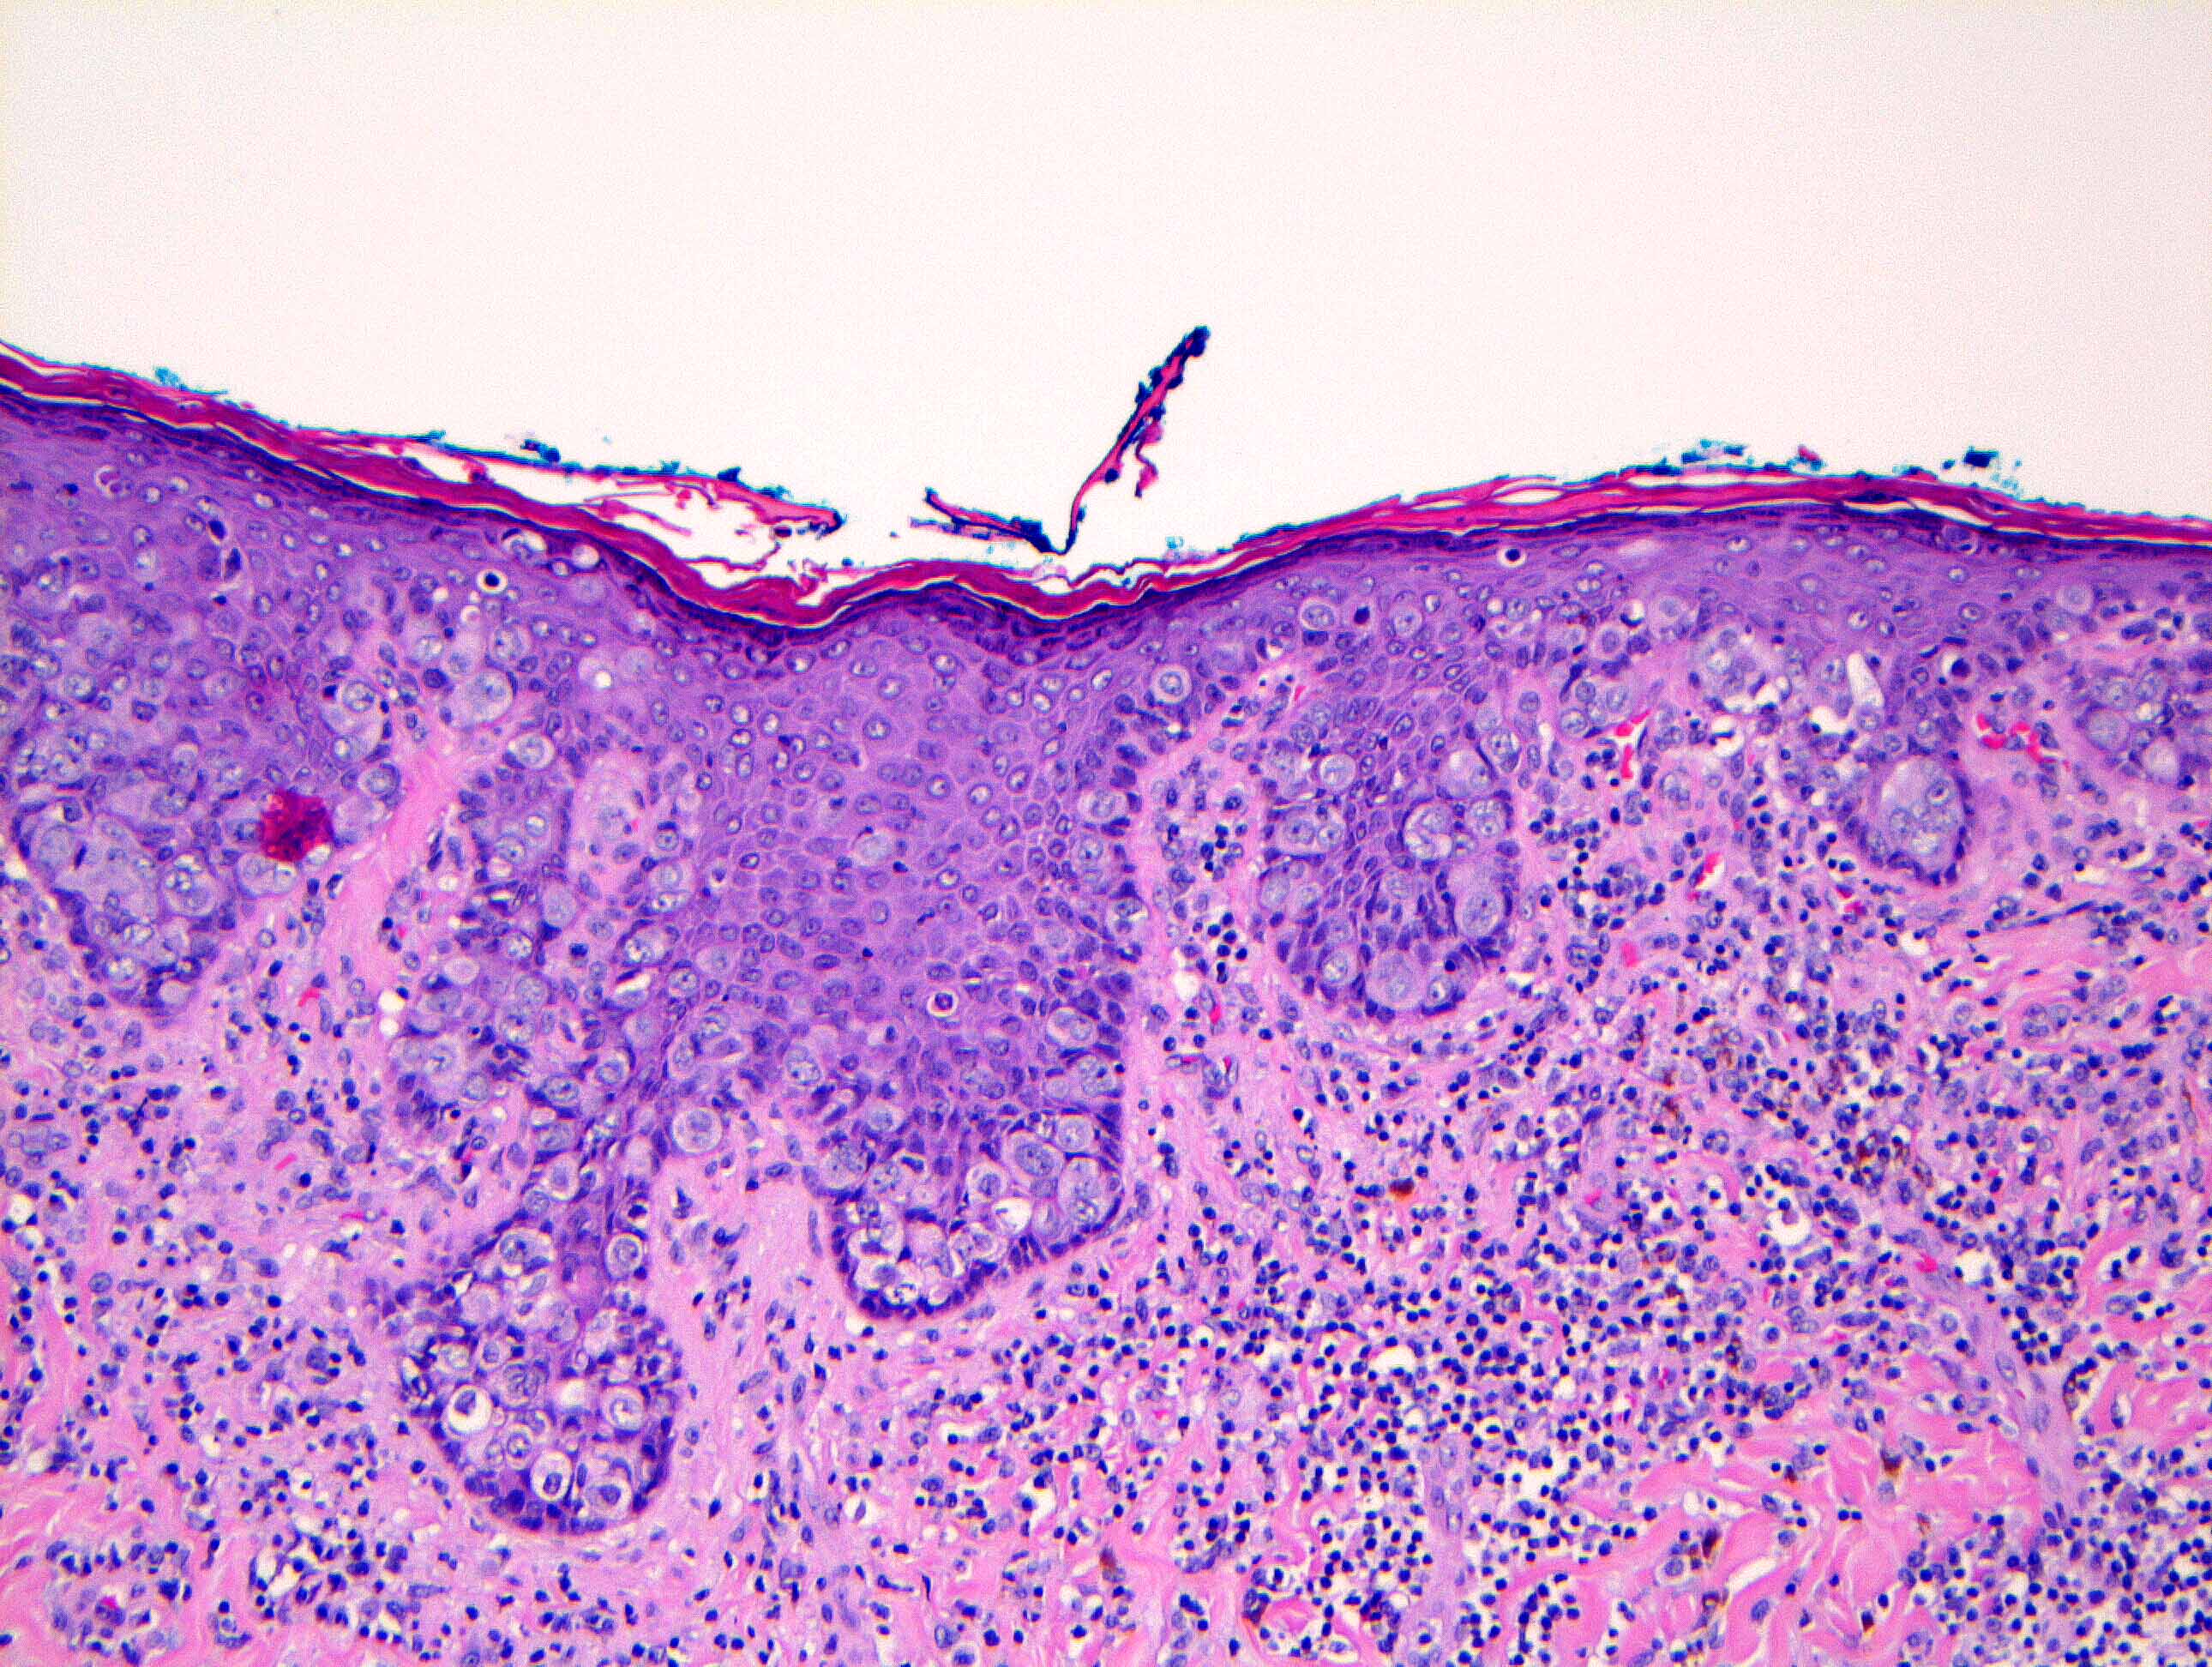

Microscopic (histologic) description

- Single cells or clusters of cells spread throughout the epidermis

- Cells have abundant pale cytoplasm, large irregular nuclei with prominent nucleoli

- Underlying dermis may have chronic inflammation

- Epidermis with hyperkeratosis and possibly ulceration

- Florid cases can show gland formation

- Paget cells may phagocytose melanin, mimicking melanocytes

- Underlying carcinoma is most commonly high grade invasive carcinoma of no special type (NST; 53 - 64%) or DCIS (24 - 43%) (Histopathology 2020;77:181)

Microscopic (histologic) images

Contributed by Anna Biernacka, M.D., Ph.D. and Mary Ann Gimenez Sanders, M.D, Ph.D.